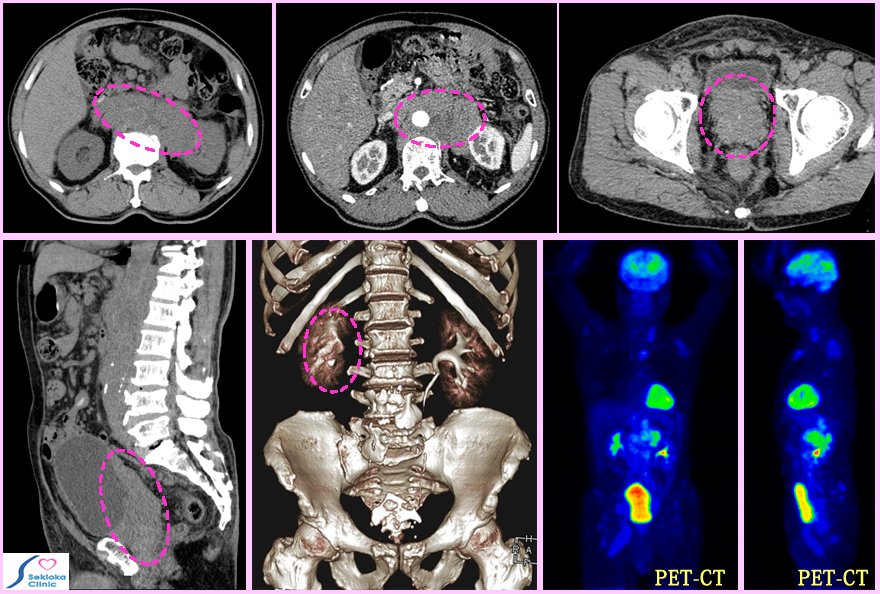

| 自覚症状 | 初期は殆ど自覚症状がなく、骨や他の部位に転移して転移部位で腫瘍が大きくなると自覚症状が現れることが多い。添付画像は便秘が出現してきて、腹部CTで検査したところ上段左の破線円内に腹部大動脈周囲リンパ節の著明な腫大を認め診断のきっかけになった例です。 |

| 診断 | 前立腺癌の場合、腫瘍マーカーの感度が他の腫瘍に比べて高く、定期健診の血液検査項目に40歳以上ではよく入れますPSA値が高いと前立腺を直腸内に指を入れて後方から触診(癌の場合、表面が粗造で固い)、次に超音波エコーで検査、超音波エコ-下に針で前立腺を穿刺して一部組織を採取し、 顕微鏡でがんの特徴があるか調べます。この生検による病理組織検査で診断されると,前立腺内にがんはとどまるのか、周囲に浸潤して広がっているのか、遠隔転移しているのか調べ、治療方針を決めます。本例は下段左の画像から、直腸と膀胱後部の間に浸潤し、骨盤内リンパ節にも転移して、下段中央の画像では右尿管は圧排され水腎症になりつつあります。PET-CTでは骨盤、脊椎、胸部の骨に転移(青く明るい部分)を認めます。上段右の画像は前立腺ですが大きく辺縁が不整です。上段中央は リンパ節腫大が膵癌や腹部の他の癌の転移による可能性がないのか、造影MDCTで検査を行い確認した画像で、下段中央の腎臓・尿管の画像もその時得られたものです。 |